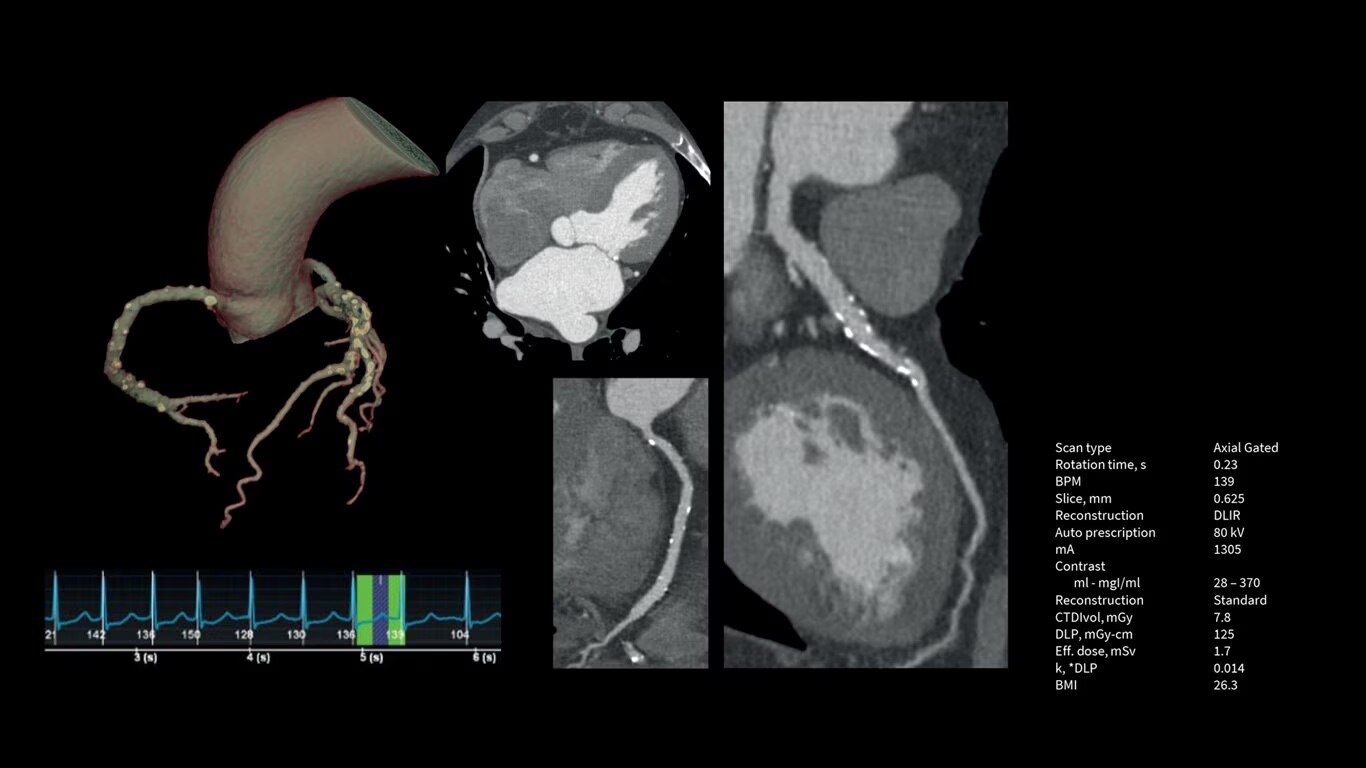

Upgrade to the industry's fastest rotation time

The Revolution Apex platform allows you to upgrade your gantry rotation speed. You can start with 0.28 sec gantry rotation time, and at any point in time when you need to advance your cardiac capability, you can upgrade to 0.23 seconds per rotation with the industry’s fastest rotation time.

Power like never before

The Revolution Apex platform provides high power output. The ability to upgrade means that siting challenges no longer prevent you from high power output to your department. If your siting power is limited to 150 KVA in the initial installation, you can start with the Power Pro option at maximum 1200 mA, and later on, you can scale up to 1300 mA Power Xtream when you upgrade the powerline.